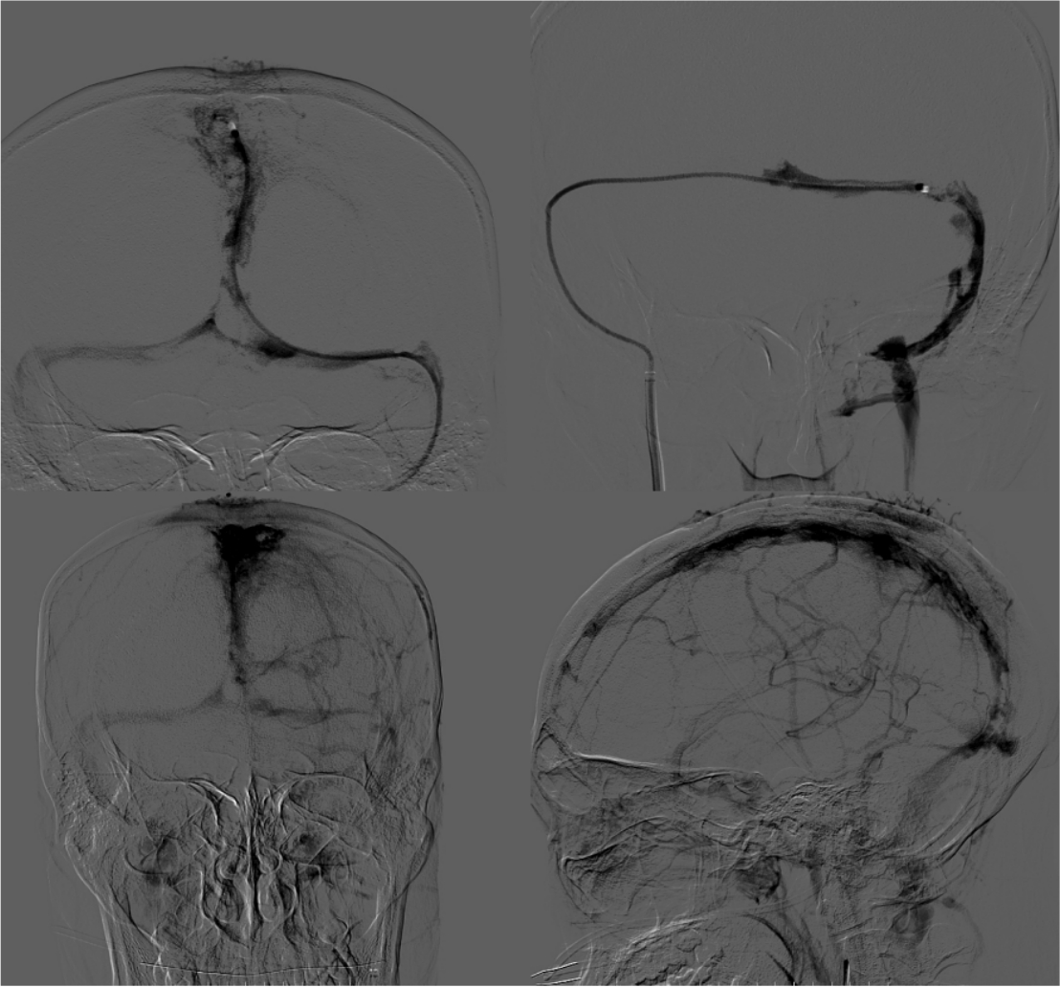

股动脉入路动脉造影显示上矢状窦后部和左侧横窦不显影,静脉期显影延迟,皮层静脉开放并明显增粗; 股静脉入路超选颅内静脉,微导丝和微导管引导ACE抽吸导管超选颅内静脉窦造影显示上矢状窦后部和左侧横窦内血栓影。

在静脉窦内造影显示血栓负荷量明显减少,静脉窦再通, 再次动脉造影显示静脉窦内血流恢复,窦内血流稍慢。